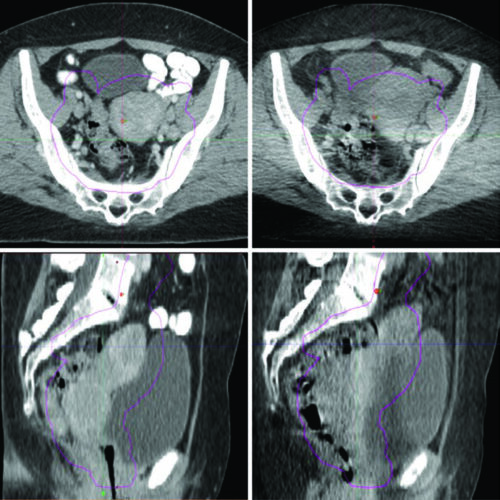

Delineamento de Volumes

Guias práticos de delineamento de volumes-alvo e órgãos de risco por sítio anatômico na radioterapia.